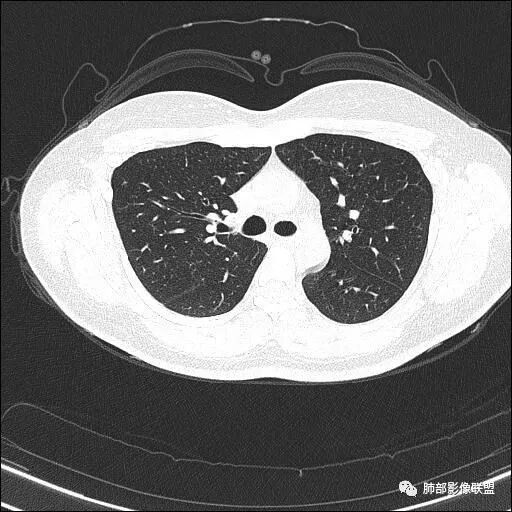

中年女性,体检发现, 双肺上叶多发囊腔伴斑点,斑片影,囊腔壁不规则,部分内见分隔,部分可见树芽征。考虑感染性病变,结核,NTM可能。

中年女性,体检发现, 双肺上叶多发囊腔伴斑点,斑片影,囊腔壁不规则,部分内见分隔,部分可见树芽征。考虑感染性病变,结核,NTM可能;建议密切随访左上肺胸膜下囊性灶。

年轻女性,血常规正常,体检发现,影像表现:双上肺多发空洞及空腔样改变,薄壁为主,部分壁不规则,伴不规则分隔,疑似鬼脸征,多数位于胸膜下。诊断:1、隐球,年轻女性,体检发现,血常规正常,多数胸膜下,疑似鬼脸征,必须首先考虑。2、结核,发病部位支持,多发空洞样病变支持,但无临床症状,病灶形态太单一,无树芽征,可能性不大。3、PLCH,无吸烟史,无临床症状,可能性小。4、寄生虫,无嗜酸增高,无IGE增高,可能小,5、空腔性转移,无原发灶,年轻较小,暂不支持。6、多中心原发腺癌,空腔周围无明确边界清楚的GGO,年轻。可能小。7、NTM,无支扩,可能小。8、风湿类疾病,无相关病史,无相关自身抗体结果,暂不支持。综上,考虑隐球菌可能大。先查隐球荚膜抗原。必要时穿刺活检。

大雄: 青年女性,双上肺多发不规则薄壁空洞伴少许结节,部分洞内有分隔,病灶多位于胸膜下,无症状,血象正常。影像比较怪异,可能得疾病谱有:隐球,结核,寄生虫,NTM,类风湿结节,空洞型转移,PLCH结核无明显气道播散树芽,寄生虫嗜酸细胞不高,NTM无症状,类风湿结节与转移少见上叶优势分布,PLCH一般有吸烟史。综上,先考虑隐球菌,建议查隐球抗原

2.双肺多发薄壁空洞影、条索影及结节影,边界较清楚,密度偏高不柔和,散乱,但有成簇倾向或堆积感,胸膜下分布为主,双肺上叶分布为主。

1.年轻女性,缺乏临床表现,多发空洞及结节影、条索影,上肺胸膜下分布为主,临床实践中常见肺病是什么?正如部分老师分析的—继发性肺结核!